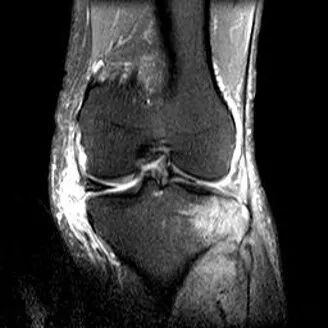

1、宽度减小,在通过半月板体部的冠状面上蝶形消失,同时可见内移的半月板位于髁间窝、交叉韧带旁2、矢状面示残余的前角或后角变小或截断3、半月板前(后)角增宽或双半月板前(后)角征4、双前交叉韧带或双后交叉韧带征

桶柄状撕裂:宽度减小,在通过半月板体部的冠状面上蝶形消失,同时可见内移的半月板位于髁间窝、交叉韧带旁